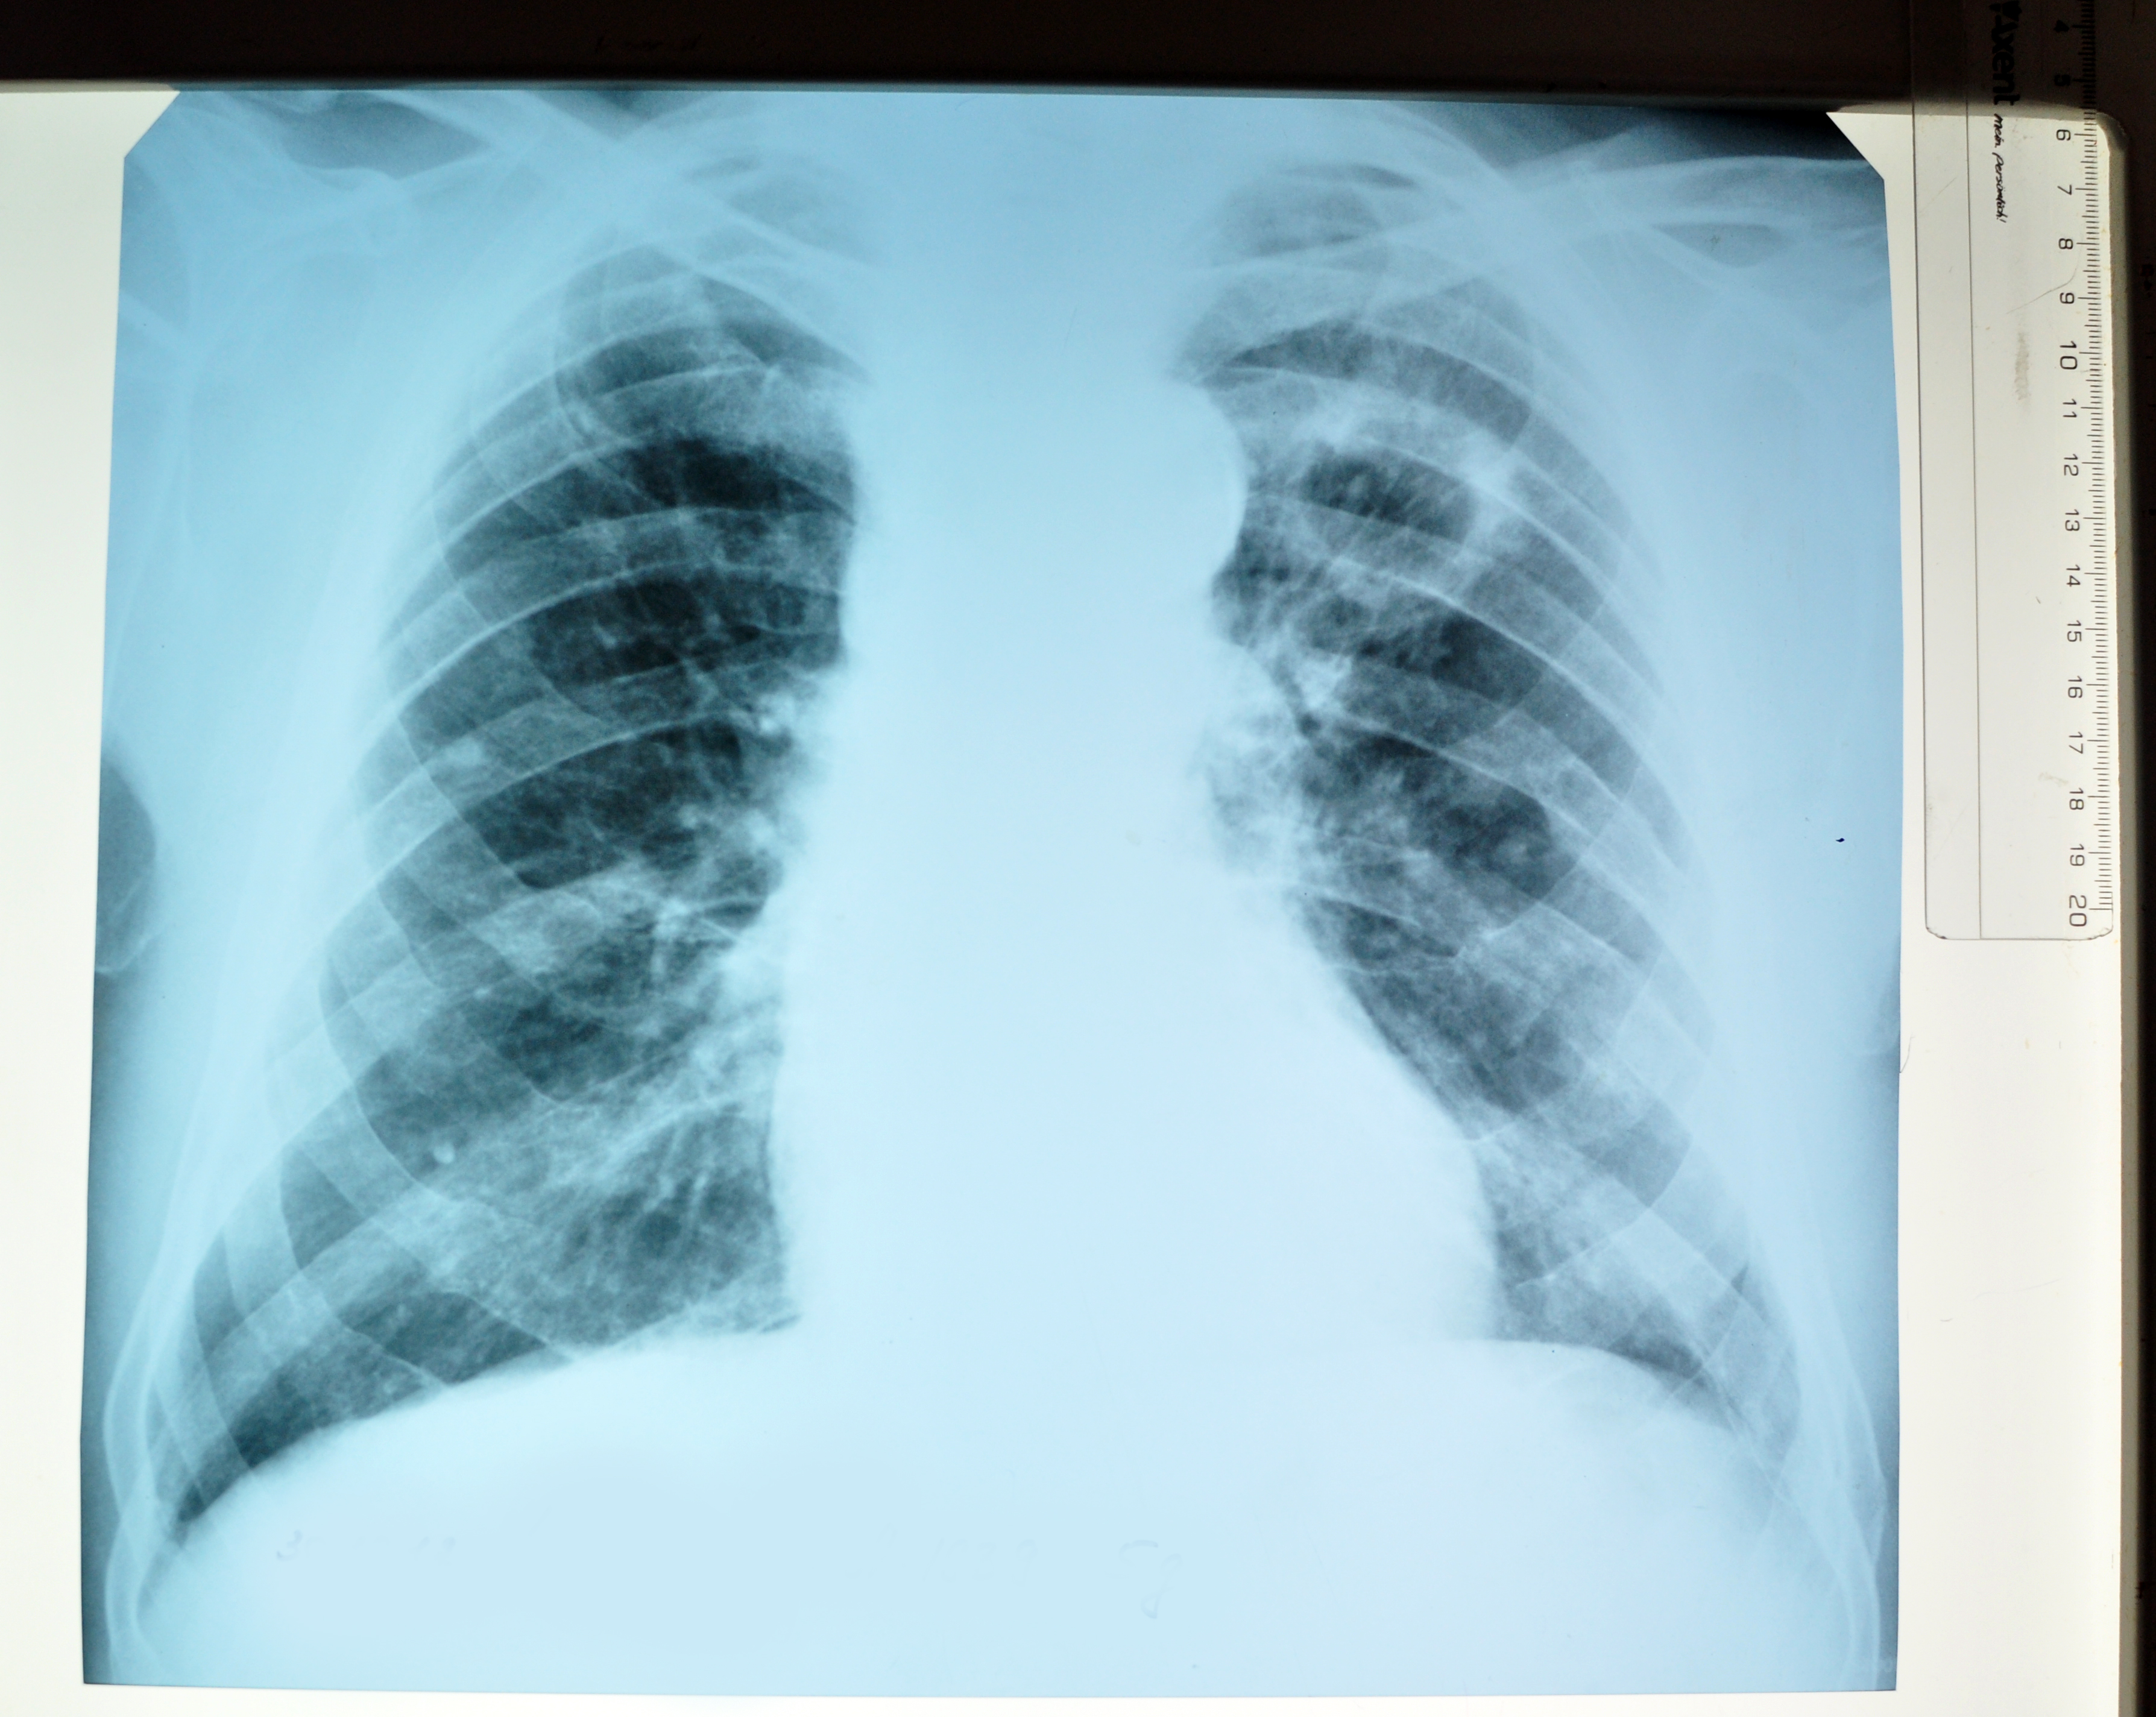

Снимок легких при туберкулезе является важным методом диагностики этого заболевания. На рентгеновских снимках можно увидеть изменения в легких, которые свойственны туберкулезу.

Рентген грудной клетки туберкулез

Рентген грудной клетки туберкулез

Рентгенография грудной клетки туберкулез

Туберкулез рентген снимки

25

Рентгенография грудной клетки туберкулез

Туберкулёз лёгких на рентгене

Туберкулез легких рентген

Рентген грудной клетки туберкулез

Рентген грудной клетки туберкулез

В данной статье представлены многочисленные фотографии снимков легких при туберкулезе, чтобы помочь вам понять, как выглядят изменения легких на рентгеновских снимках при этом заболевании.